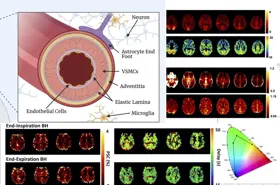

We work on creating image acquisition and analysis methods for obtaining quantitative physiological information from both healthy and diseased tissue. We are particularly interested in imaging vascular pathologies, hypoxia in tumours, and neurodegeneration. Our research incorporates a variety of MRI techniques including Oxygen Enhanced MRI, arterial spin labelling, T1, T2 and T2 mapping, and diffusion imaging. In addition, we have ongoing research using transcranial Doppler ultrasound, near infrared spectroscopy, pupillometry, PET and CT. The group is working towards the clinical translation of these emerging methods, and thus we concentrate on using short, patient-friendly paradigms.